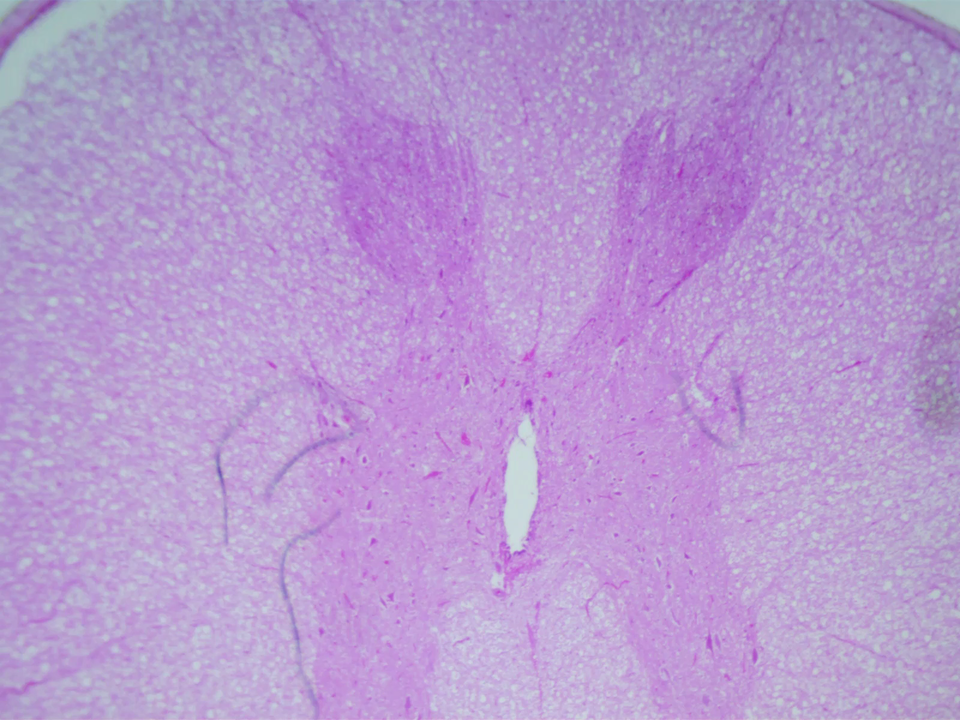

Za pomocą wirtualnego mikroskopu przeprowadzono obserwację przekroju poprzecznego przez rdzeń kręgowy. Rdzeń kręgowy zbudowany jest z istoty białej (wypustki neuronów), która otacza leżącą wewnątrz istotę szarą (skupisko ciał neuronów). Na przekroju poprzecznym istota szara (wybarwiona na ciemniejszy kolor) przybiera charakterystyczny kształt zbliżony do litery H. Jej pasma tworzą skierowane ku przodowi rogi brzuszne (przednie) oraz zwrócone ku tyłowi rogi grzbietowe (tylne). W centralnej części rdzenia kręgowego znajduje się kanał środkowy (wypełniony płynem mózgowo‑rdzeniowym). W powiększeniu czterokrotnym widoczna jest niewyraźnie struktura przypominająca kształt litery H lub skrzydła motyla. W środku struktury jest pionowy, biały, podłużny otwór, to kanał środkowy. Istotę szarą (literę H) wypełniają jasno- i ciemnoróżowe komórki. Wokół litery H jest istota biała. Wypełniają ją jasnoróżowe i białe komórki. W powiększeniu dziesięciokrotnym widoczna jest niewyraźnie górna część struktury przypominająca kształt litery H (lub skrzydła motyla), wypełniona drobnymi jasno- i ciemnoróżowymi komórkami. W środku struktury jest kanał środkowy. Jest on pionowy, biały, podłużny, a jego górny koniec jest wrzecionowaty. Wokół litery H znajduje się istota biała wypełniona jasnoróżowymi i białymi komórkami. W powiększeniu czterdziestokrotnym widoczna jest struktura wypełniona drobnymi jasno- i ciemnoróżowymi komórkami. Ciemnoróżowe komórki są kuliste, zebrane w skupiskach.